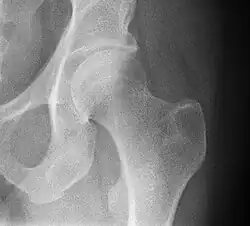

![]() Bones of the hip region | |

![]() Right hip of a female human | |